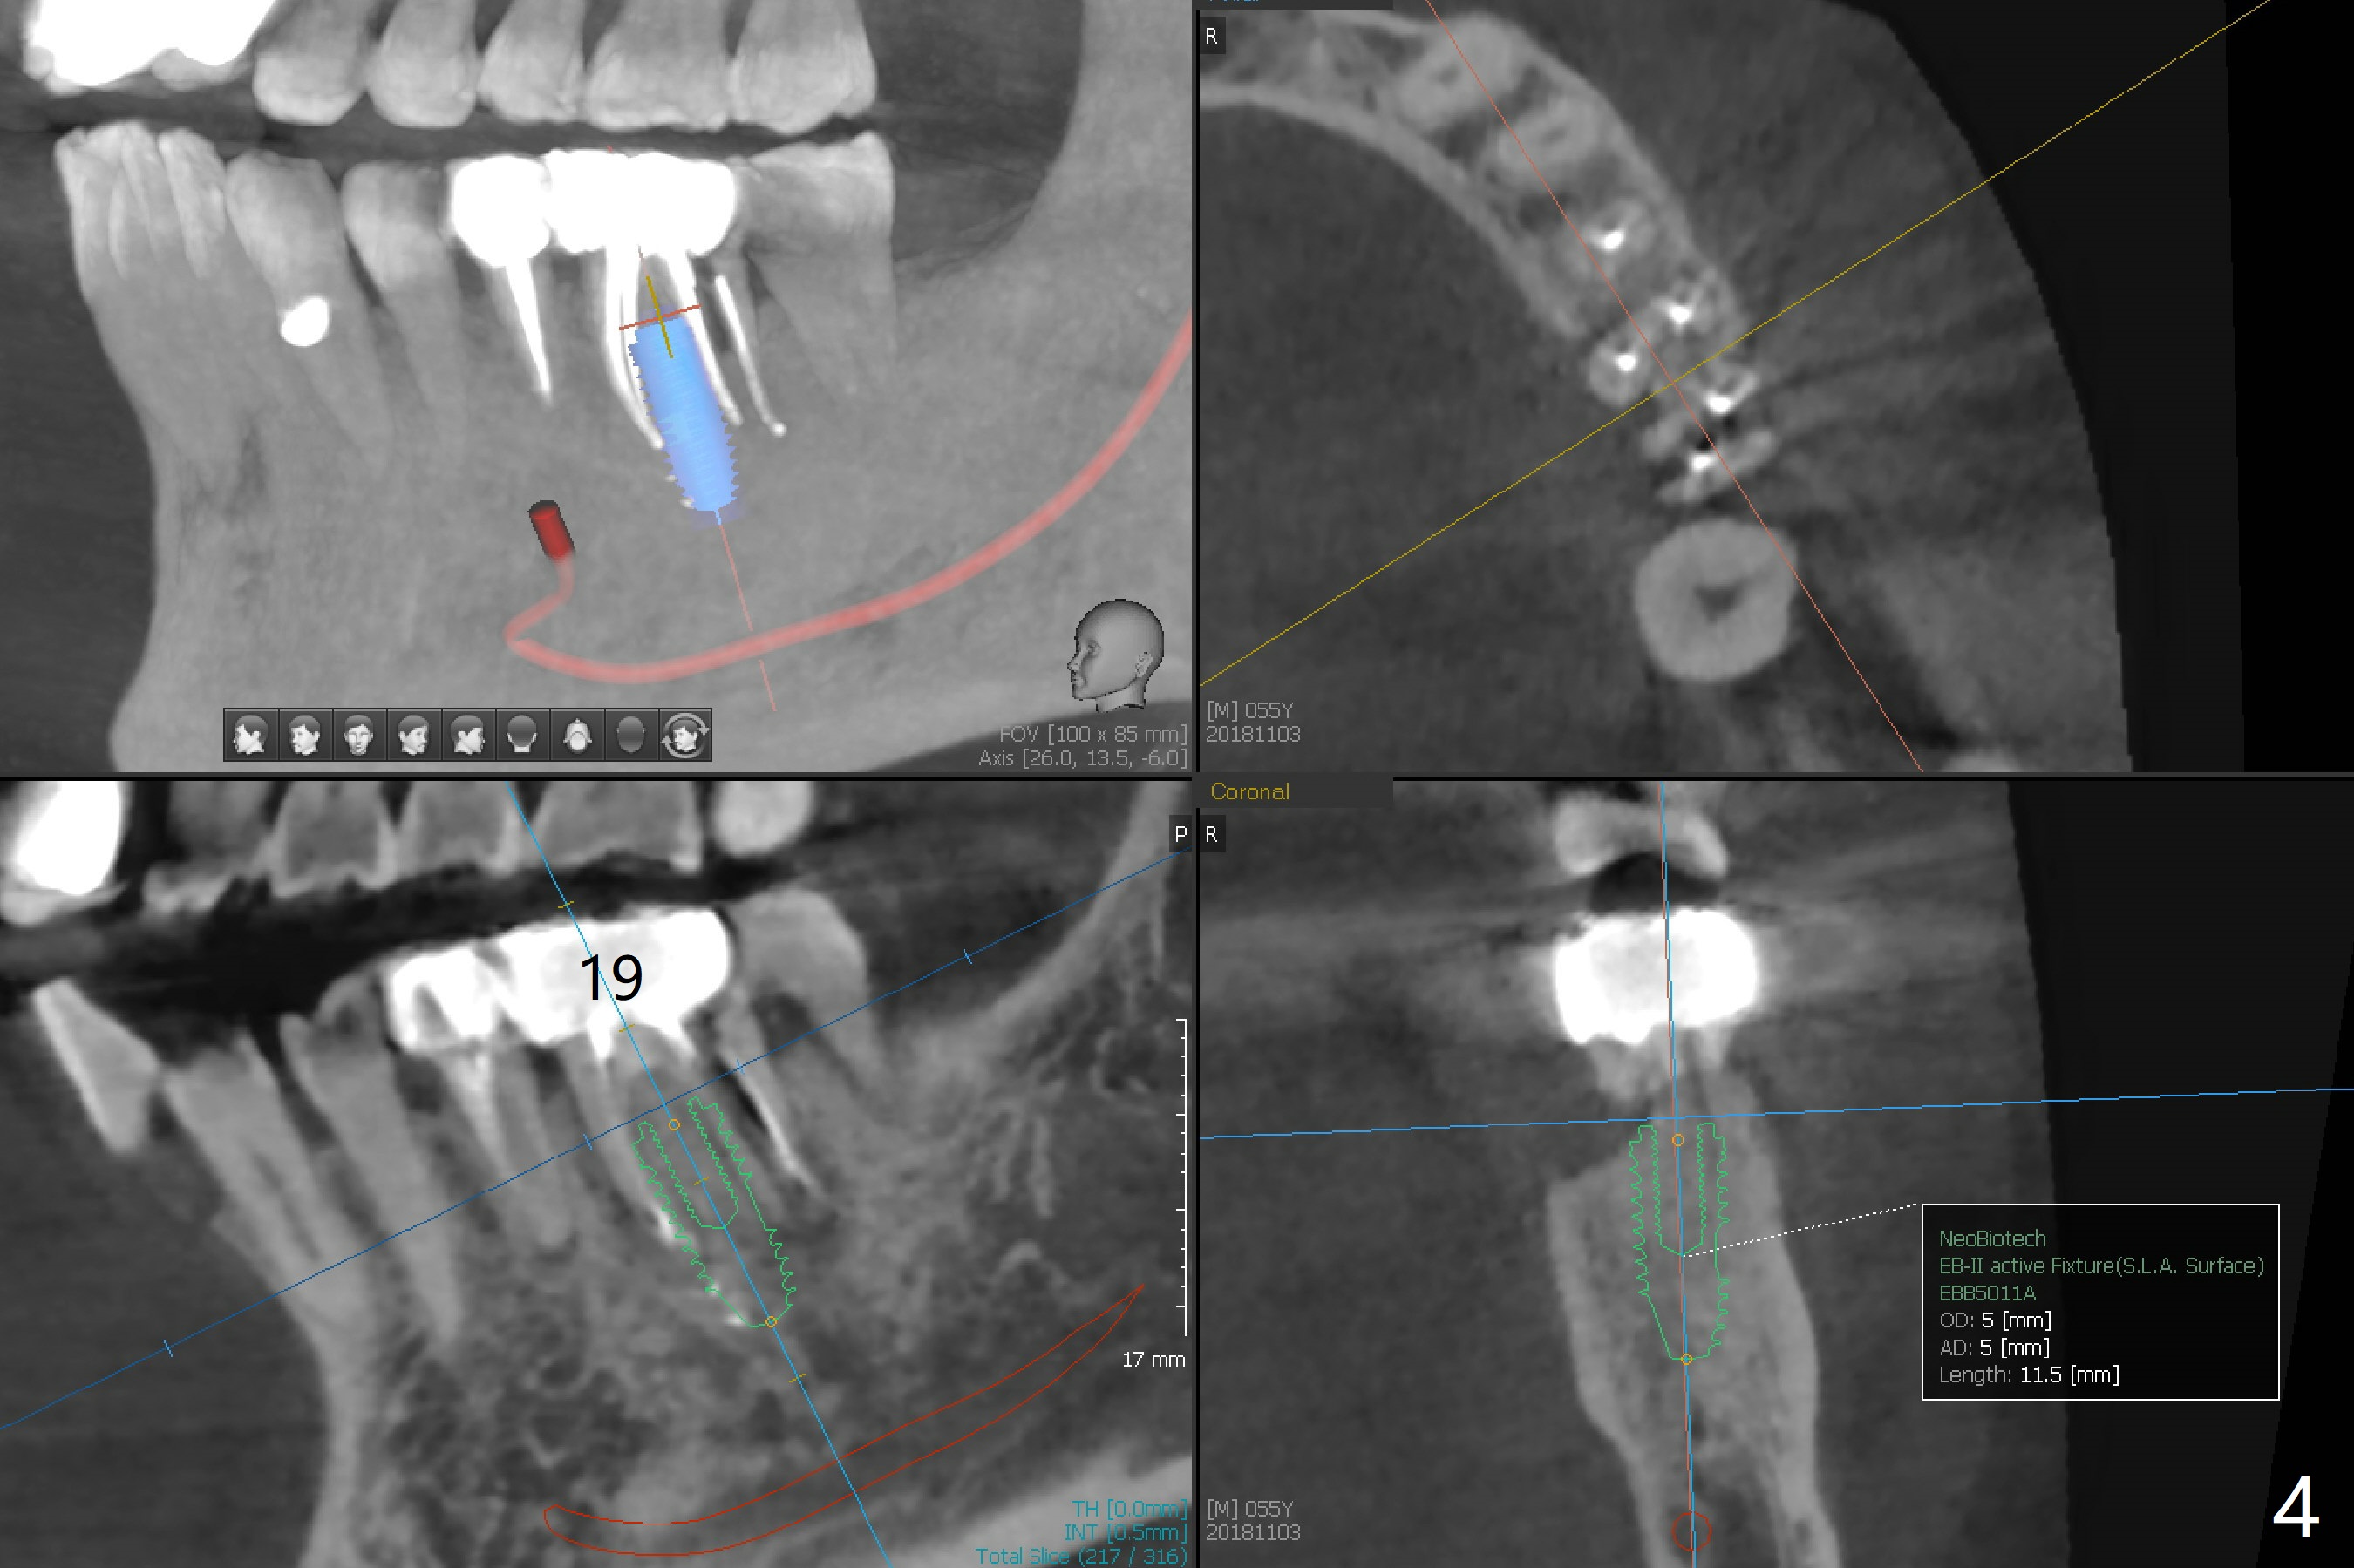

A 55-year-old man with chronic sinusitis, gagging and bruxism returns for #2 implant redo nearly 4 months post implant removal and bone graft (Fig.1). It appears that the site heals with ~ 860 HU (Fig.2). Considering history of chronic sinusitis, a 5x10 mm implant seems too long (Fig.3). For active gag reflex, a 5x11.5 mm implant may be also too long at #19 (Fig.4).